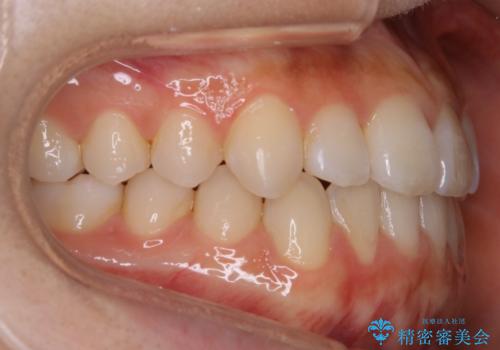

【非抜歯】受け口の改善 10代で始める本格的噛み合わせ治療

- 受け口の改善と前歯のガタつきの治療を主訴にご来院されました。

こちらの患者様の場合、上の前歯のガタつきが原因で口を閉じる際に上下の前歯の先端同士が先に当たってしまい、そこからさらに深く噛み込もうとすると下顎が前にずれていってしまうという、機能性の反対咬合であることが検査の結果わかりました。

そのため、まずは上顎の前歯のガタつきを改善していき、前歯が先に当たってしまうという症状を改善し噛み込む位置を後方の本来の位置に誘導する方法をとりました。